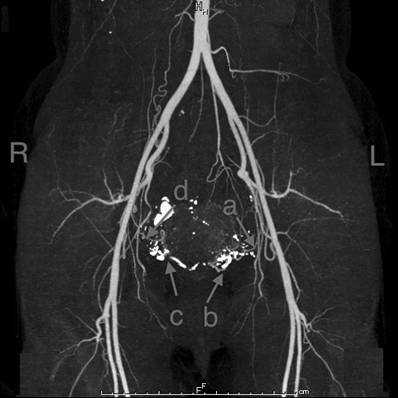

Figures 1 and 2 show the blood vessel distribution in the uterus for both patients. Figure 3 shows the blood distribution in the normal uterus after the delivery. Identification of blood vessels was performed by a radiologist (M.T).

Fig 1

3-D computed tomography (CT) imaging of patient 1. a: Left uterine artery. No descending branch was seen. b: New vessels probably arisen from ascending branch of left uterine artery. c: New vessels probably arisen from ascending branch of right uterine artery. d: Right uterine artery. No descending branch was seen. Identification of each vessel was made by a radiologist (M.T).

In vaginal RT, we usually amputate the cervix at the level of the uterine artery, which corresponds to approximately 10 mm below the isthmus. In this procedure, we usually ligate and cut the descending branches of the uterine arteries and vaginal arteries. These arteries mainly supply blood to the lower segment of the uterus. Fig. 1 and Fig. 2 show that the descending branches of uterine arteries and vaginal arteries could not be seen in either patient. New arterial vascularization from the ascending branches of uterine arteries arose, and these new vessels seemed to supply blood to the remaining cervix, including the neo-cervix. On the 3-D CT scan, no ischemic areas were seen in the remaining uterus.